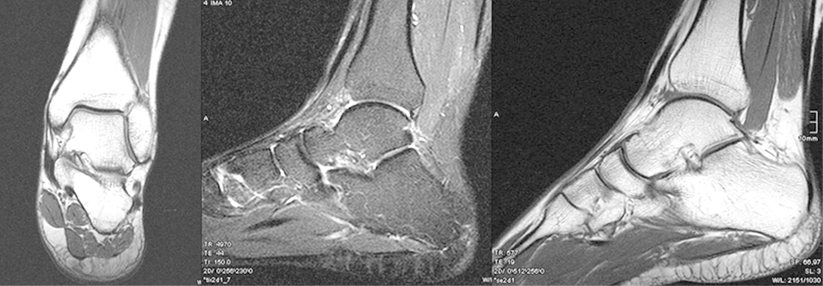

Distorsion im oberen Sprunggelenk ist mehr als nur ein Bagatelltrauma: Instabilität bei bis zu jedem Fünften

„Das stellen wir sechs Wochen ruhig und dann heilt das Gelenk schon wieder.“ Einige Kollegen glauben, bei einer Distorsion im oberen Sprunggelenk…